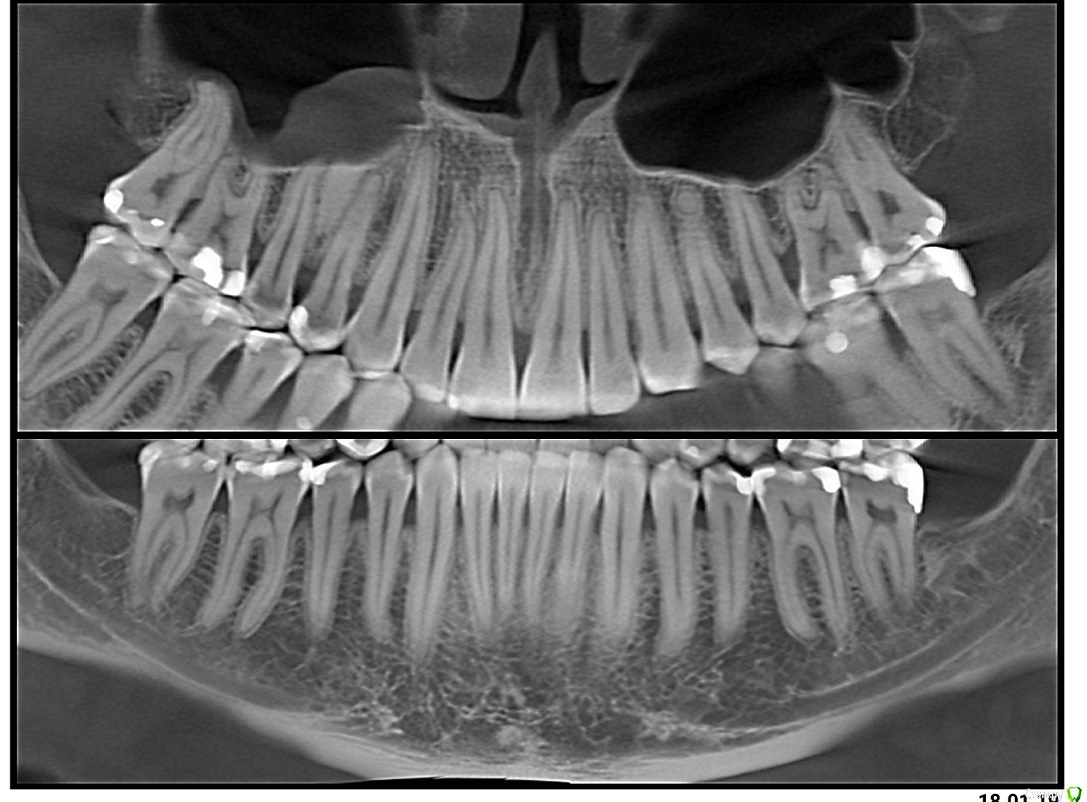

1. рецессии, клиновидный дефект, ВНЧС в результате неправильного прикуса (макрогнатия нижней и микрогнатия верхней челюсти)

3. сейчас уже пол года мы увеличиваем в длину верхнюю челюсть, что бы наконец устранить причину всего. Потом будем брекетами выпрямлять все оставшееся.

Я вижу вариант, полного протезирования всех зубов нижней челюсти, максимально закрыв отсутствующие сосочки. Если я понимаю правильно, то зачем тогда нам выпрямлять зубы нижней челюсти, травмируя кость и провоцируя дальнейшие рецессии? Не правильнее ли с помощью протезирования сразу придать им нужную форму и положение? Тем более раскрыв скученный перед у нас там дыры такие же как в боковых отделах будут...

ссылка на КТ недельной давности

https://www.dropbox.com/sh/x75s1nxcm3ez5uj/AAD-7PRrFsY2xmGAuhlWjwp2a?dl=0